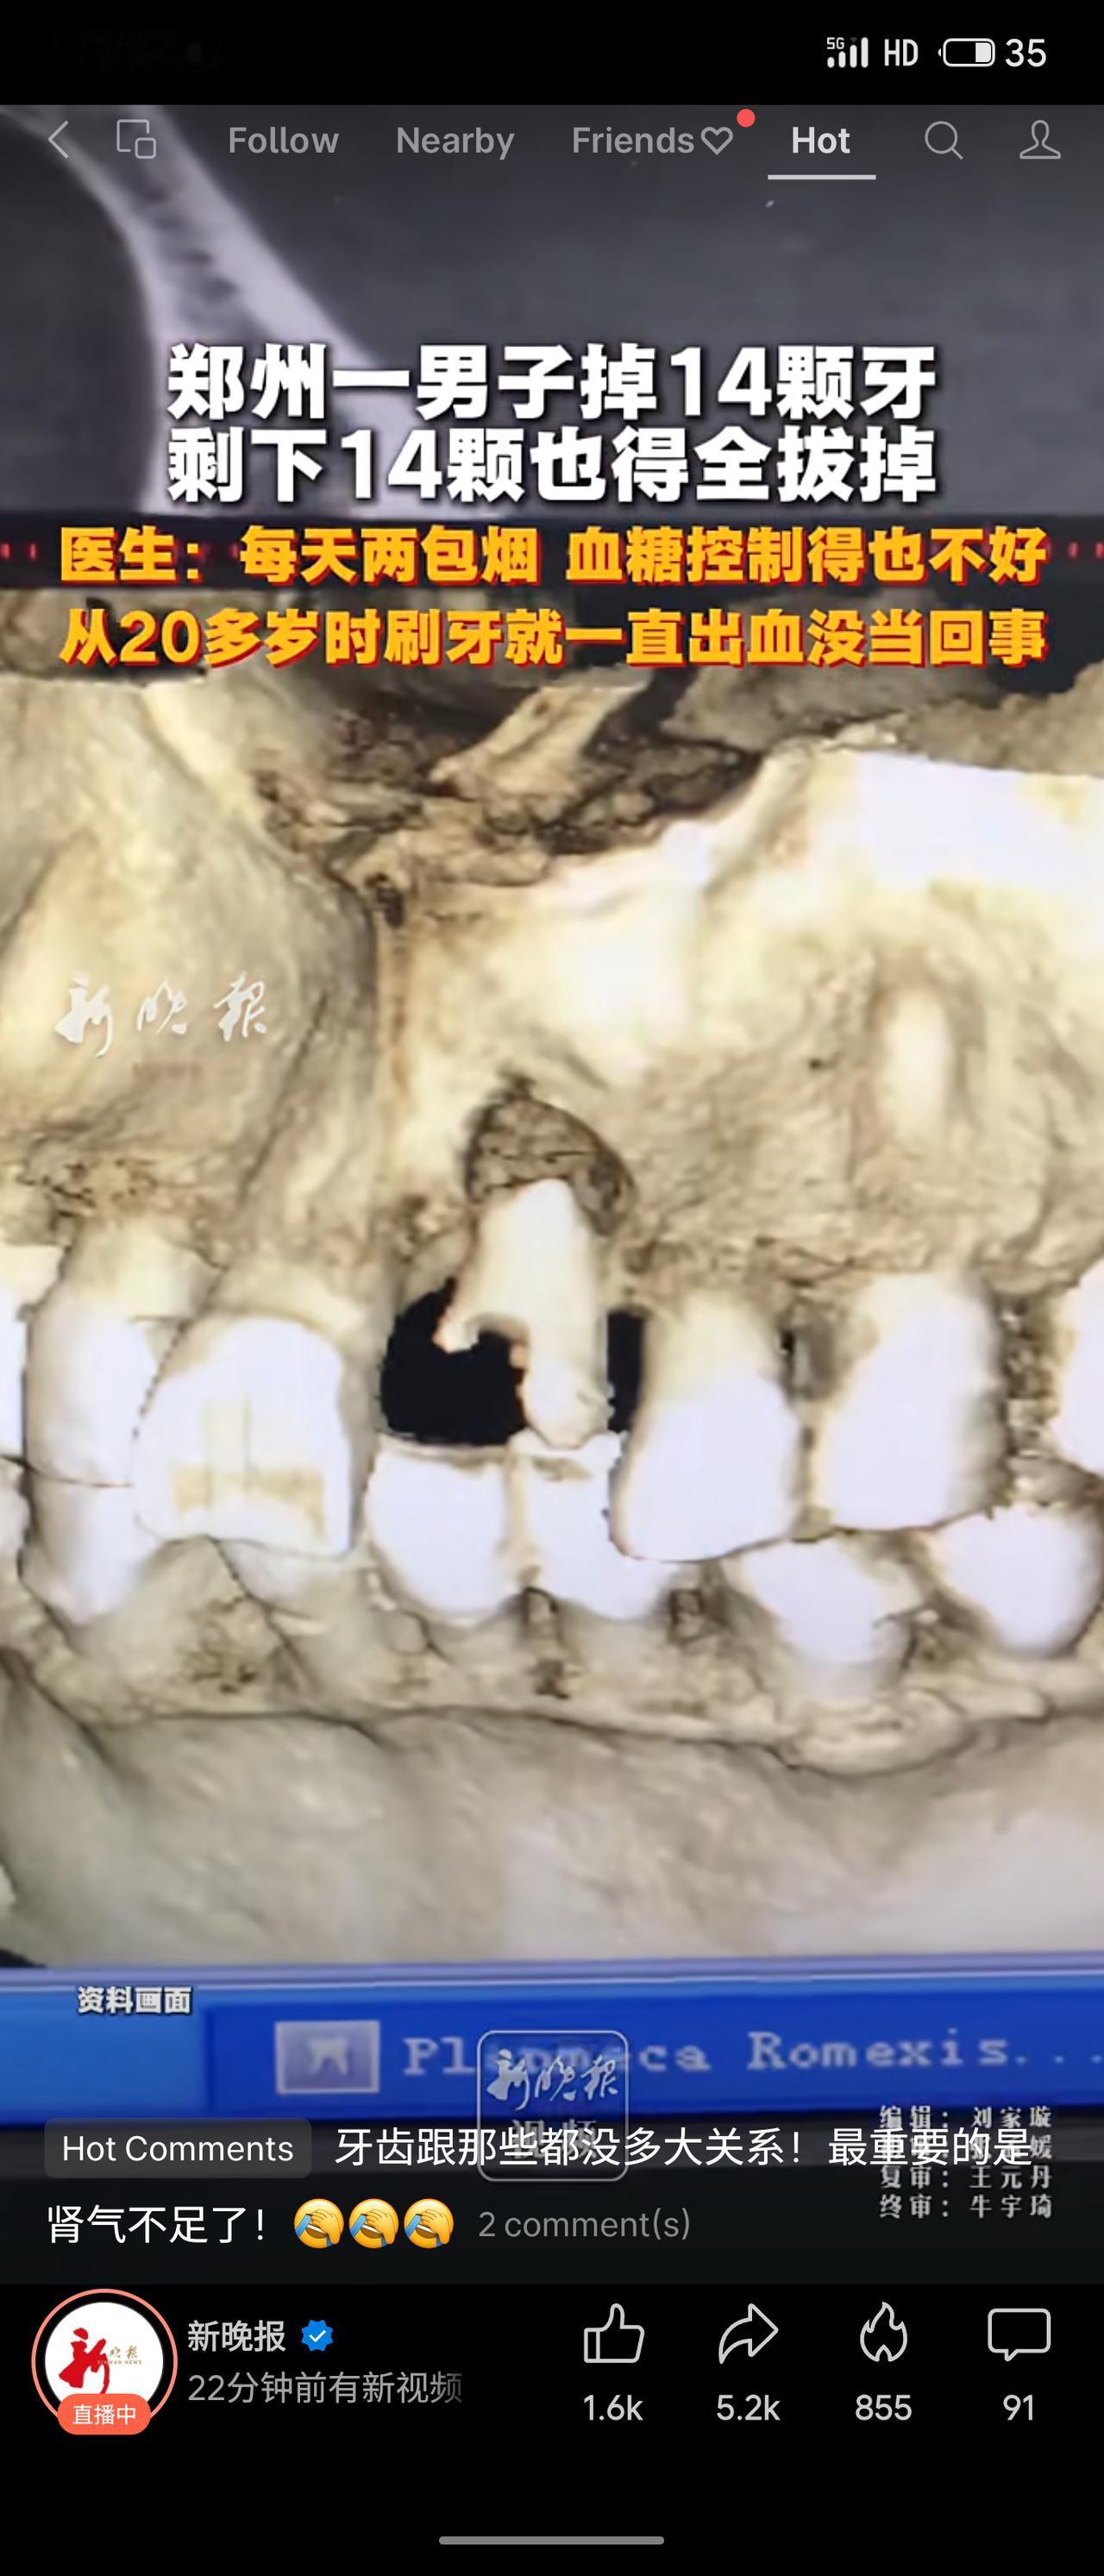

郑州一男子20多岁起刷牙出血未在意,每天两包烟且血糖控制不佳,最终掉14颗牙,剩下14颗也需全拔掉。医生指出主因是吸烟与糖尿病。